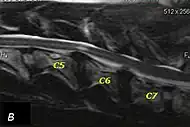

The disease tends to be gradually progressive. Symptoms such as weakness, ataxia, and dragging of the toes start in the rear legs. Dogs often have a crouching stance with a downward flexed neck. The disease progresses to the front legs, but the symptoms are less severe. Neck pain is sometimes seen. Symptoms are usually gradual in onset, but may progress rapidly following trauma.[6] X-rays may show misaligned vertebrae and narrow disk spaces, but it is not as effective as a myelogram, which reveals stenosis of the vertebral canal. Magnetic resonance imaging has been shown to be more effective at showing the location, nature, and severity of spinal cord compression than a myelogram.[7] Treatment is either medical to control the symptoms, usually with corticosteroids and cage rest, or surgical to correct the spinal cord compression. The prognosis is guarded in either case. Surgery may fully correct the problem, but it is technically difficult and relapses may occur. Types of surgery include ventral decompression of the spinal cord (ventral slot technique), dorsal decompression, and vertebral stabilization.[8] One study showed no significant advantage to any of the common spinal cord decompression procedures.[9] Another study showed that electroacupuncture may be a successful treatment for Wobbler disease.[10] A new surgical treatment using a proprietary medical device has been developed for dogs with disc-associated wobbler disease. It implants an artificial disc (cervical arthroplasty) in place of the affected disc space.[11]

Wobbler disease is probably inherited in the Borzoi, Great Dane, Doberman, and Basset Hound.[2] Instability of the vertebrae of the neck (usually the caudal neck) causes spinal cord compression. In younger dogs such as Great Danes less than two years of age, wobbler disease is caused by stenosis (narrowing) of the vertebral canal[3] related to degeneration of the dorsal articular facets and subsequent thickening of the associated joint capsules and ligaments.[1] A high-protein diet may contribute to its development.[4] In middle-aged and older dogs such as Dobermans, intervertebral disc disease leads to bulging of the disc or herniation of the disc contents, and the spinal cord is compressed.[3] In Great Danes, the C4 to C6 vertebrae are most commonly affected; in Dobermans, the C5 to C7 vertebrae are affected.[5]